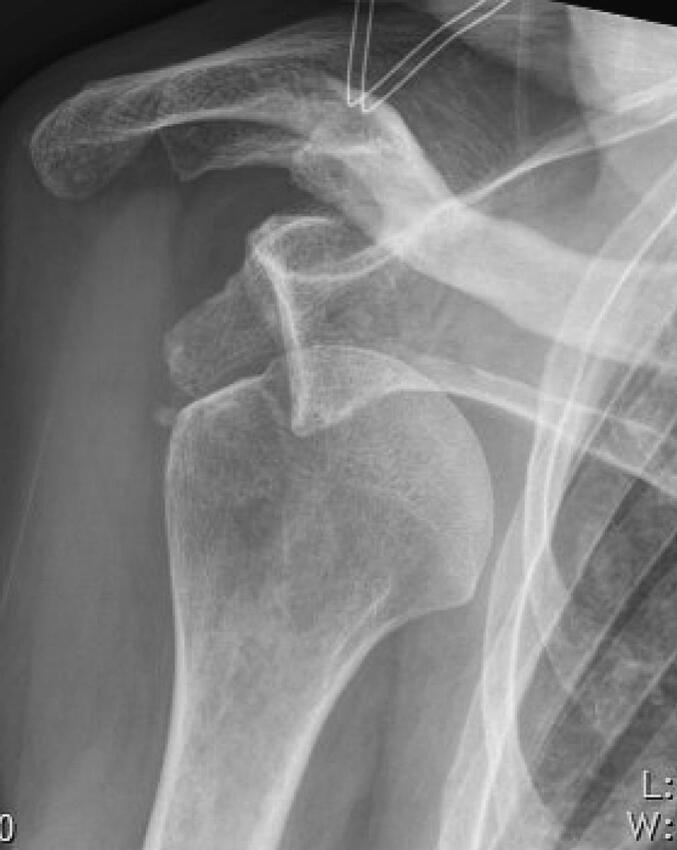

We report the case of an 80-year-old man who suffered an anteroinferior shoulder dislocation with rupture of the rotator cuff following a fall. An attempt at closed reduction under analgosedation resulted in extensive skin laceration on the elbow and forearm. The wound treatment was complex and resulted in numerous complications.

我们报告了一例80岁男性病例,该患者在跌倒后发生了肩前下脱位并伴有肩袖破裂。在镇痛镇静下尝试进行闭合复位,结果导致肘部和前臂出现大面积皮肤撕裂伤。伤口处理复杂,引发了诸多并发症。